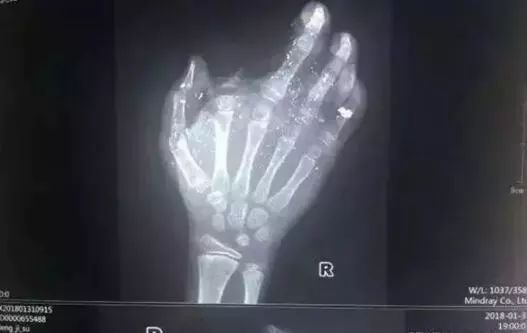

2018年1月,广西发生一起手机爆炸事件,一名年仅12岁的小男孩手掌被炸得血肉模糊,右手食指被炸没了,拇指、中指、无名指也都炸伤,失去了供血,手掌皮肤被炸得稀烂。